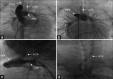

Isolation of the left common carotid artery (LCCA) is a very rare congenital aortic arch anomaly. We present this finding in a female infant with pulmonary atresia and intact ventricular septum, with a clinical diagnosis of CHARGE syndrome. Cardiac catheterization revealed an anomalous origin of the LCCA from the pulmonary trunk, with retrograde filling of the pulmonary trunk seen during left subclavian artery injection. The LCCA was ligated during central shunt placement.